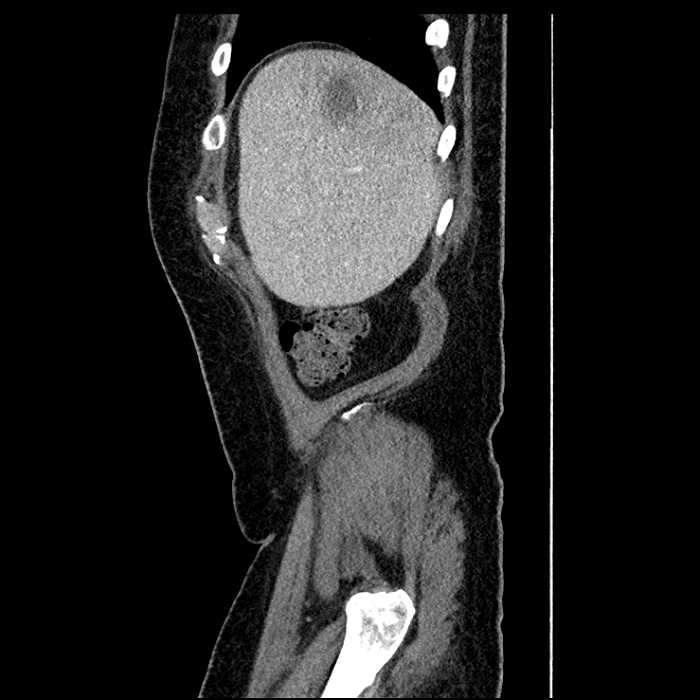

Age: 63

Sex: Male

Indication: Abdominal pain

• Large fluid density structure in hepatic segments 7 and 8 measuring 10 x 7 x 7 cm with internal septation and circumferential ill-defined low density compatible with edema

• Peripherally enhancing subcapsular collections along the anterior margin of the left hepatic lobe measuring 3 x 1 cm and 2 x 1 cm

• Clearly marginated fluid density structure in segment 7 and several other scattered tiny hypodensities, which likely represent cysts

• Hepatic abscess

Acute sigmoid diverticulitis complicated by a small contained perforation and a large abscess in the right hepatic lobe. Additional small subcapsular abscesses along the anterior margin of the left hepatic lobe.

• The classic CT imaging appearance is a double target sign with internal low density surrounded by an internal enhancing rim (capsule) and a low density external rim (edema)

• Abscesses may be unilocular or multilocular

• Gas is present in a minority of cases

Hepatic abscess showing the double target sign with low density internally surrounded by a thin inner enhancing rim (red arrow) and ill-defined outer low density rim (yellow arrow). Blue arrow indicates an internal septation. Red arrows: additional smaller subcapsular abscesses. Red arrow: focal contained perforation associated with diverticulitis.